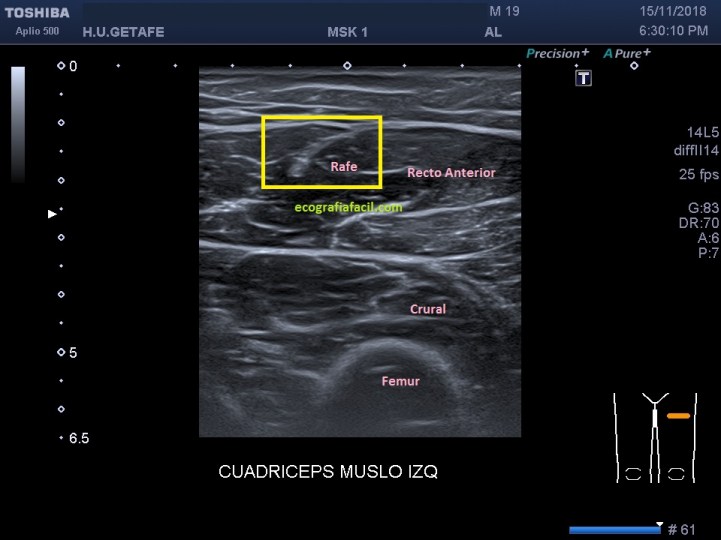

Paciente varón de 19 años, practica fútbol habitualmente, desde hace meses (no sabe precisar) y después de haber sufrido una lesión durante un partido al golpear el balón nota deformidad en la cara anterior del muslo izquierdo en el tercio proximal y dolor mientras hace ejercicio físico.

Empiezo la ecografía y compruebo una hendidura en la región afectada descrita anteriormente por el paciente. El lado contralateral parece normal. El Recto anterior izquierdo muestra en la zona «hundida» una imagen hiperecogénica y heterogénea en el teórico lugar del Rafe (flechas rojas), que en la porción más distal de la imagen heterogénea e hiperecogénica anteriormente descrita, es normal.

Imagen 2 , normal, imagen 1 y 3, patológico.

A 19-year-old male patient regularly practices football for months (he does not know how to specify) and after having suffered an injury during a match when hitting the ball, he feels deformity on the front of the left thigh in the proximal third and pain while exercising physical.

I start the ultrasound and check a cleft in the affected region described above. The contralateral side seems normal. The left anterior rectum shows in the «sunken» zone a hyperechogenic and heterogeneous image in the theoretical place of the Rafe, which in the most distal portion of the heterogeneous and hyperechogenic image described above, is normal.

Image 2, normal, image 1 and 3, pathological.